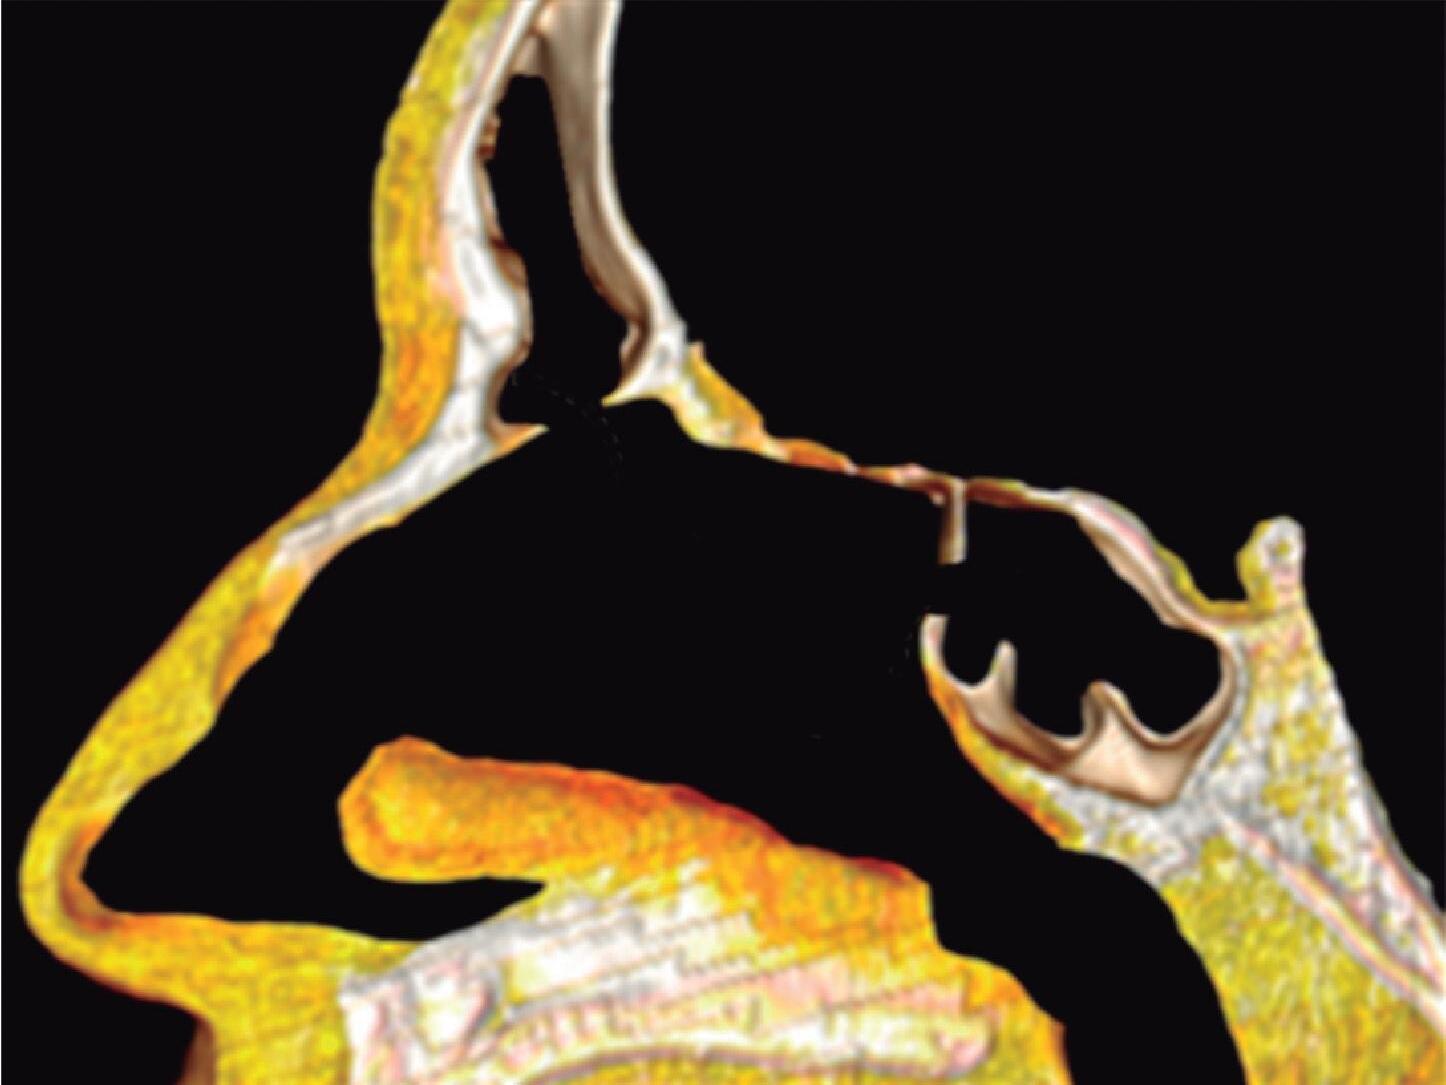

Fig. 1-20. Reconstrução tridimensional de TC demonstrando a lamela basal situada posteriormente à bulha etmoidal, acoplada à parede medial da órbita, fechando a câmara anterior: verde – concha média; vermelho – bulha etmoidal; amarelo – parede medial da órbita; lilás – processo uncinado.

A placa das conchas, juntamente com a concha média, é mantida arquitetonicamente estável por lamelas ósseas (lamelas basais da concha média e superior) que vão terminar na parede medial da órbita e no piso da fossa anterior.

As lamelas da placa das conchas são irregulares, tendo, com frequência, várias subdivisões, na maioria das vezes não paralelas e que formam no seu conjunto uma estrutura constituída por cavidades desiguais e definitivamente limitada pelo piso da fossa anterior, superiormente, e pela lâmina papirácea externamente. Por seu aspecto complexo esta estrutura por vezes é chamada de “labirinto”.

Lamela Basal Porção oblíqua que parte da face meatal da concha média e se insere na lâmina papirácea e base do crânio. É a parede posterior do meato médio, ou o limite posterior da câmara anterior.